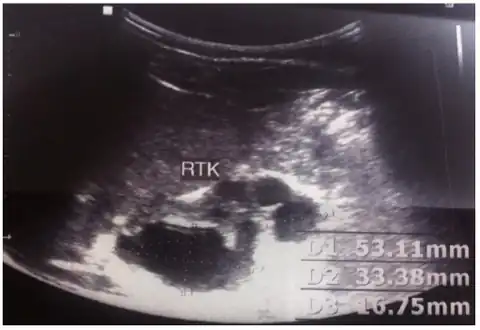

MCDK is usually diagnosed by ultrasound examination before birth. Mean age at the time of antenatal diagnosis is about 28 weeks[10] A microscopic analysis of urine in individuals with probable multicystic dysplastic kidney should be done.[8]One meta-analysis demonstrated that unilateral MCDK occurs more frequently in males and the greater percentage of MCKD occur on the left side of the body.[11]

Right dysplastic kidney with the largest cyst size measuring 33.16mm